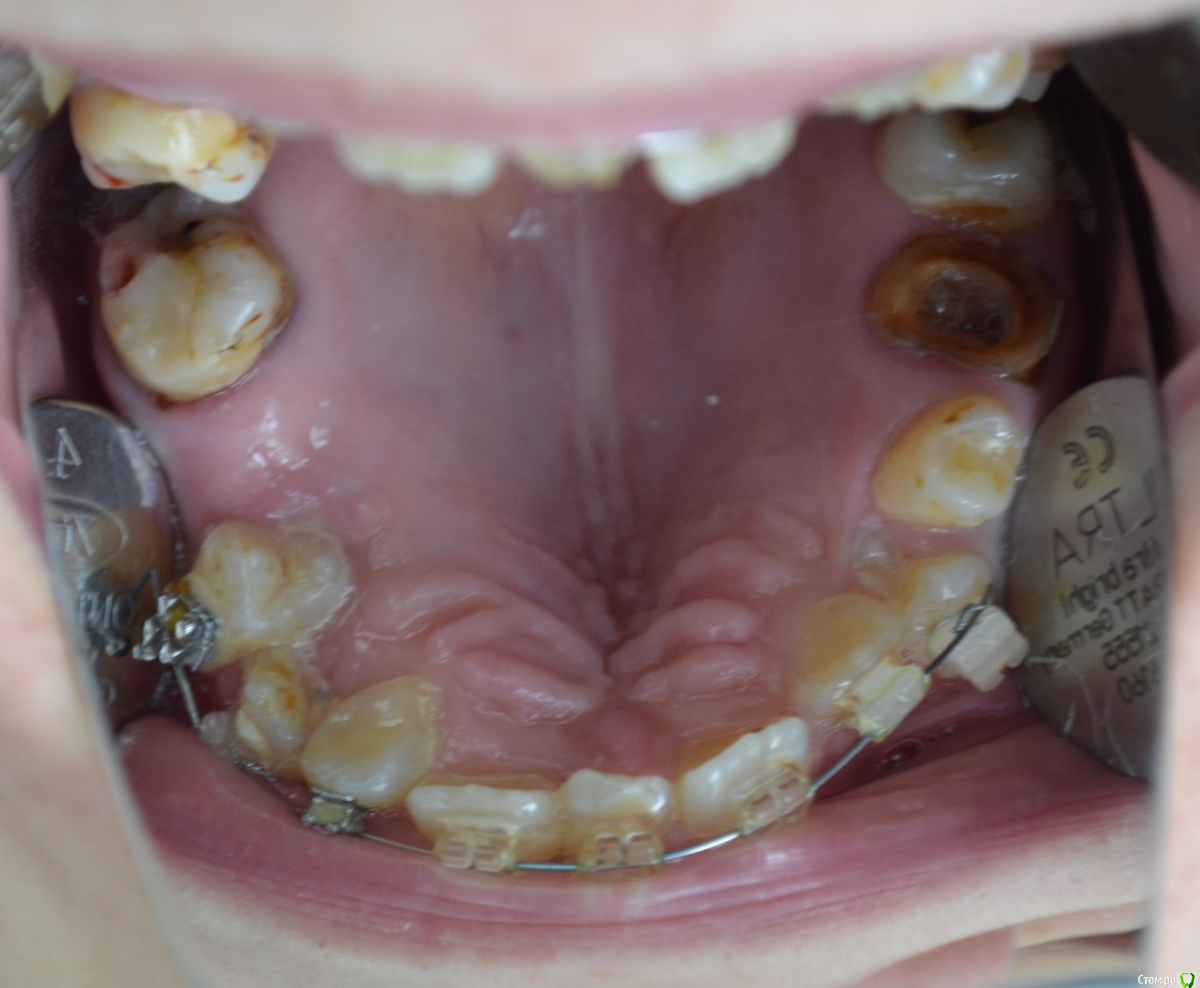

nikor117 Опубликовано 14 октября, 2015 Поделиться Опубликовано 14 октября, 2015 Здравствуйте, уважаемые коллеги.Извиняюсь за качество фото. Хотелось бы помочь пациентке 28 лет. В общем ситуация видна по фото. Сам я ортопед опыта в таких ситуациях нет, возможно подскажете куда ей стоит обратиться. Заранее спасибо. Если нужна дополнительная информация скажите постараюсь выложить. Ссылка на комментарий

nikor117 Опубликовано 14 октября, 2015 Автор Поделиться Опубликовано 14 октября, 2015 Возможность красиво улыбаться, с ее слов на ортодонтии она уже порядка 8 лет, брекеты стоят 1.5 или 2 года, сама врач, сложность ситуации представляет, хочет услышать совет Ссылка на комментарий

Yana guapa Опубликовано 14 октября, 2015 Поделиться Опубликовано 14 октября, 2015 эти фото были ведь на соседнем форуме "...." . там были советы, и хирурги и ортодонты отписывались. причем не так давно. и фото были без брекетов, до начала лечения (около 6 месяцев назад). не похоже на 1.5 года с брекетами здесь . тем, что у нее на зубах стоит сейчас - не помочь это точно. 4 Ссылка на комментарий

Monkey Опубликовано 18 октября, 2015 Поделиться Опубликовано 18 октября, 2015 (изменено) и мне, пожалуйста у пациентки похоже синдром Крузона Изменено 18 октября, 2015 пользователем Monkey 1 Ссылка на комментарий